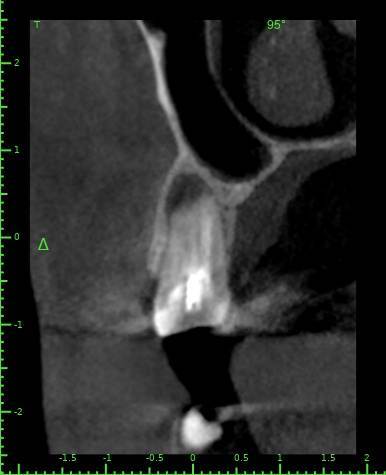

Здравствуйте, появился полгода назад свищ на десне, заполняется и лопается, затягивается и снова появляется, спустя пару месяцев обратился в стоматологию, на снимке ничего критичного не увидели, отправили домой наблюдать тип, еще прошло 3 месяца, так и не проходит и хуже не стало, болей нет никаких, только небольшая если трогать в районе свища, пойдя в другую стоматологию, сделали снимок и так же непонятно что и почему, пошел на КТ, и обратно в стоматологию, есть какая то полость, можно попробовать но нет гарантии, что пройдет, прикрепляю снимок К

ТРезультаты и плюс программа для открытия